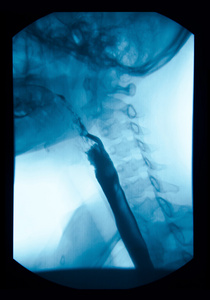

该图像的 x 射线上消化道 (ugi) 瘘孔闭合照片